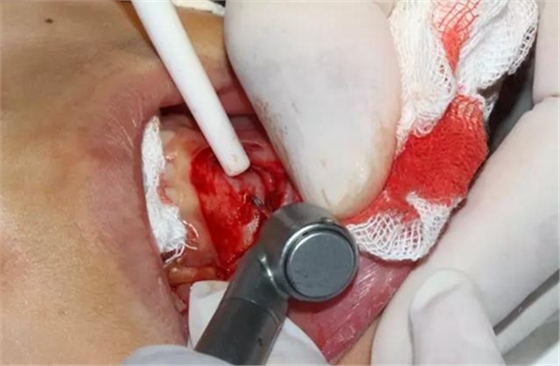

口腔局部浸潤麻醉,手術鋪巾

切開、翻瓣

去除骨皮質,暴露牙冠大部分